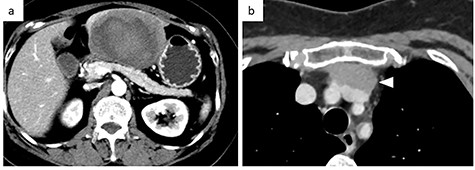

A 56-year-old woman presented to another hospital with acute abdomen. Computed tomography (CT) examination demonstrated a tumor 10 cm in diameter that protruded from the left lateral segment of the liver, with evidence suggestive of rupture of the liver tumor (Fig. 1). Since the patient was in good general condition, she was referred to our hospital for further evaluation. Her blood biochemical parameters when she was referred to our hospital were hemoglobin: 11.6 g/dl, albumin: 3.4 g/dl, γ-globulin: 18.5% and anti-acetylcholine receptor antibody: <0.3 nmol/L. Dynamic CT presented a liver tumor 10 cm in diameter, which was located at the left lateral segment of the liver, with a clear margin. A mass with an irregular margin was also identified in the anterior mediastinum (Fig. 2). On percutaneous angiography, since obvious extravasation of the contrast medium could not be identified, the arteries of the left lateral segment were embolized to prevent re-bleeding. Although a definitive preoperative diagnosis could not be made using magnetic resonance imaging (MRI) (Fig. 3), fluorodeoxyglucose positron emission tomography (FDG) showed increased FDG uptake in both the hepatic and anterior mediastinal tumors (Fig. 4). Although the liver tumor was suspected to be metastasis secondary to a thymoma based on the clinical findings, percutaneous tumor biopsy was performed to confirm the pathological diagnosis. The biopsy suggested malignant T-cell lymphoma or metastatic thymoma. In order to prevent re-rupture of the hepatic tumor, to confirm the pathological diagnosis and to potentially achieve a curative resection, the patient underwent laparoscopic left lateral segmentectomy (Fig. 5). Although the tumor was found to be adherent to the stomach, blunt dissection was possible. In addition, no peritoneal dissemination was detected. The surgical duration was 212 min and estimated blood loss was 50 ml. The liver tumor was pathologically diagnosed as metastatic thymoma type AB (Fig. 6). The patient’s postoperative course was uneventful and she subsequently underwent radical thymectomy 3 months after the liver resection. The thymic tumor was pathologically diagnosed as thymoma type B2. Currently, 30 months after thymectomy, she remains free from tumor recurrence.

Abdominal CT at the onset of symptoms suggestive of acute abdomen. A 10 cm diameter liver tumor was seen to protrude from the left lateral segment of the liver and high-density ascites was identified around the liver.